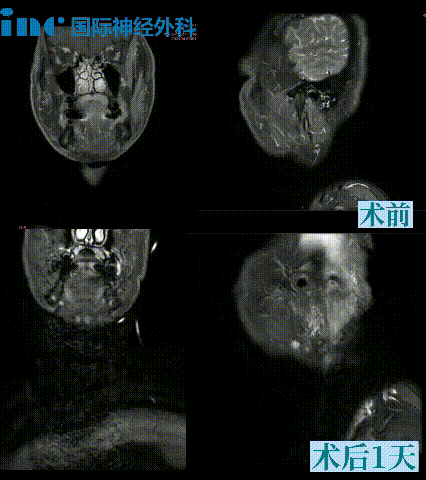

好消息是,手术过程顺利,肿瘤被完整切除,原先受压迫的颈内静脉也恢复了正常血流。患者术后颅神经功能保留良好,仅出现轻微暂时性不适,之后也完全恢复正常。复查磁共振显示肿瘤切除彻底,也没有出现新的神经功能问题。

术后MRI